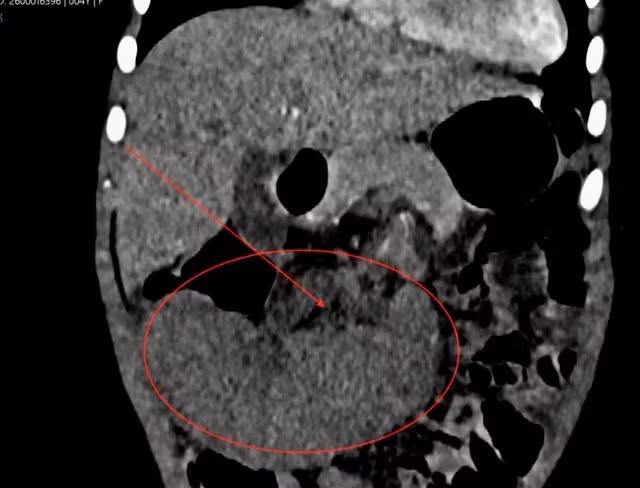

Phần lách của bệnh nhi lớn, nằm ở vị trí bất thường, lách không tưới máu...

Ngay sau đó, các bác sĩ tiến hành khám và cho bệnh nhân thực hiện các xét nghiệm. Kết quả phát hiện phần lách của bệnh nhi lớn, nằm ở vị trí bất thường, lách không tưới máu (nhồi máu lách), toàn bộ lá lách bị thiếu oxy và dưỡng chất do mạch máu nuôi dưỡng (động mạch lách) bị tắc nghẽn, dẫn đến mô lách bị hoại tử.